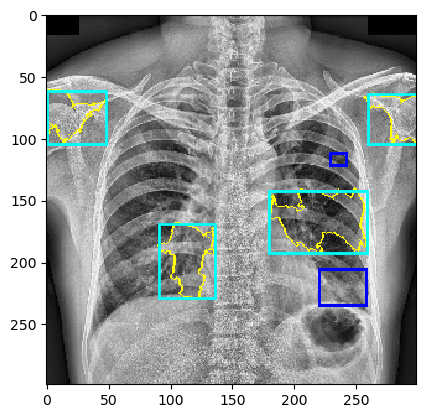

The behavior of MindfulLIME compared to LIME is demonstrated in Figures 4 and 5. Figure 4 showcases random sample 1 with a detected Pleural Effusion condition (annotations highlighted in green), while Figure 5 features random sample 2 with a detected Lung Opacity condition (annotations highlighted in blue). Each figure illustrates the disparities between the ground-truth annotations (darker-colored rectangles) and the generated explanations (lighter-colored rectangles surrounding the yellow border of the selected superpixels). We would like to emphasize that our trained classifier model generalizes well and is not simply memorizing the training data, as evidenced by its performance on a separate evaluation dataset.

The left columns depict the results for the top 1 feature, while the right columns display the results for the top 4 features. The first row presents the output of MindfulLIME, while the second and third rows represent the results of LIME using 1000 and 4000 samples, respectively. When comparing the results of LIME and MindfulLIME for two visual random samples, it becomes evident that MindfulLIME excels in multiple aspects. Firstly, MindfulLIME consistently identifies the top 1 feature with the highest similarity with the actual bounding box. Additionally, as the number of top features increases, MindfulLIME effectively prioritizes and presents more relevant features at the forefront. These findings highlight the enhanced performance and prioritization capabilities of MindfulLIME compared to LIME.